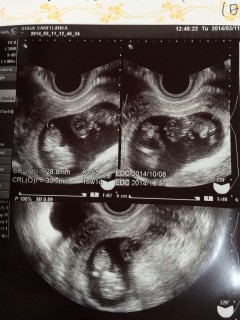

2週間ぶりの検診でクリオネのような可愛い姿に♡ 順調に成長していますよ!という先生の声が毎回励みになりますね。 つわりもだいぶ落ち着いてきた!

双子だとわかった時の初エコーです♪

可愛すぎです♪